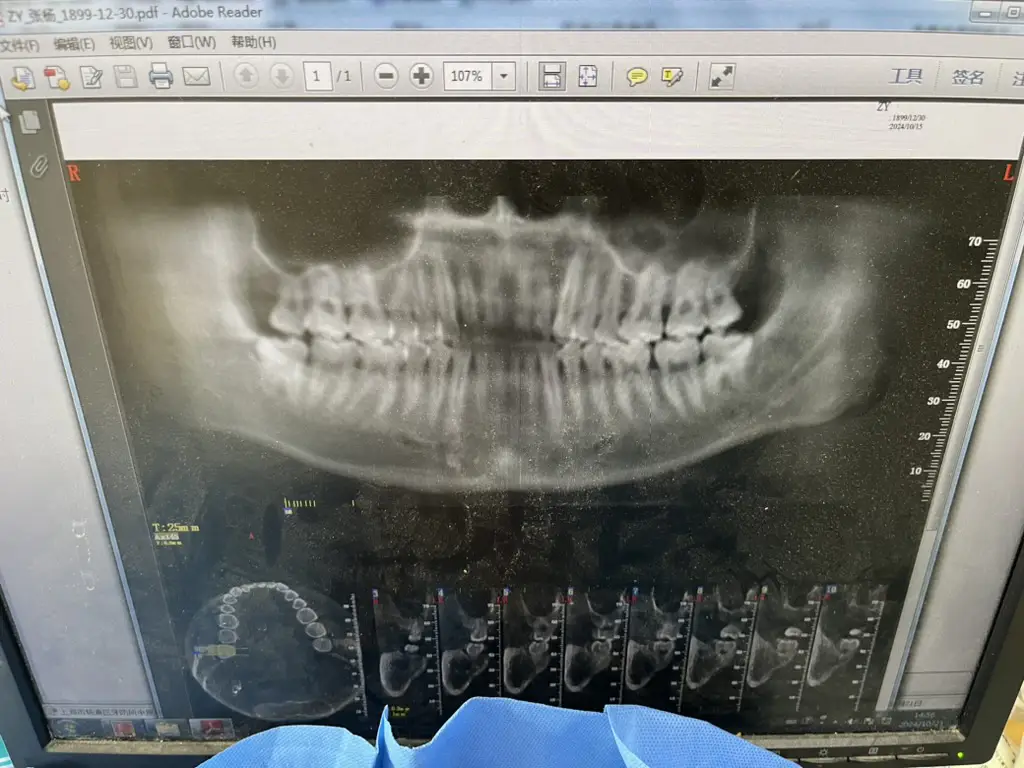

牙疼,具体来说是牙龈疼。疼得我吃嘛嘛不香、非常心烦,于是在一个平平无奇的周三,我去了一趟牙诊所。买了一个99¥的洗牙套餐,拍了一张牙片:

牙医说,我的(右下侧,牙片里是左下侧)智齿没有完全长出来,所以覆盖的牙龈和牙齿之间的缝隙很容易藏污纳垢。再加上我清洁不到位,所以就反复发炎。